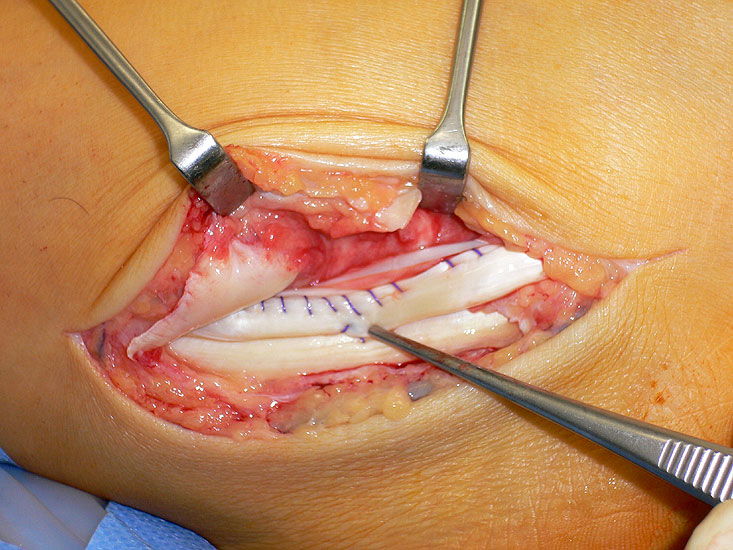

Vertiefung der Gleitrinne zur Wiederherstellung einer knöchernen Führung der Peronealsehnen.

Abbildung 10

Sämtliche operative Therapien zielen auf eine Wiederherstellung der geschädigten Struktur. Findet sich eine physiologisch ausgebildete Gleitrinne mit traumatisch rupturiertem Retinakulum, so stellt die anatomische Rekonstruktion des Retinakulums die adäquate operative Maßnahme dar. Ist gleichzeitig die Gleitrinne sehr flach aufgeprägt mit hoher Reluxationstendenz der Sehne intraoperativ, so hat sich eine gleichzeitige Vertiefung der knöcheren Gleitrinne bewährt (siehe OP Technik „Operative Therapie der Peronealsehnenluxation und Peronealsehneninstabilität“) 313233.